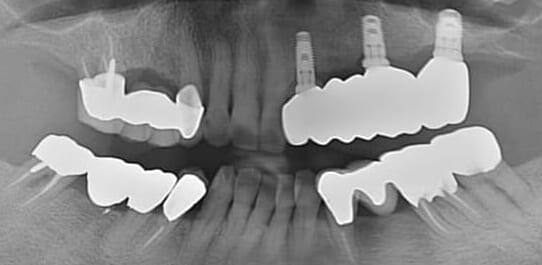

【治療前】

【治療後】

上の前歯の傾斜と下の前歯全体のズレが目立つ症例です。

昔であれば抜歯をしてワイヤー矯正をする症例ですが、当院の最新のマウスピース矯正であれば非抜歯で1年で充分に綺麗になることをご説明しました。